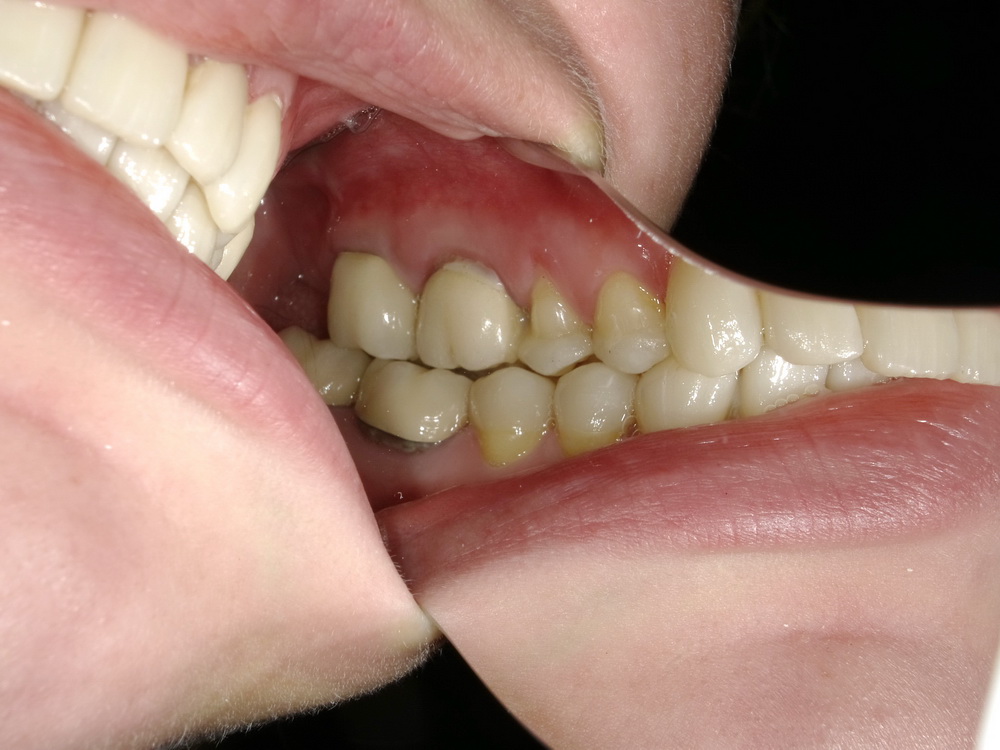

Totalrekonstruierte CMD-Patientin aus dem Münsterland zum Abschlussbefund

Die Patientin ist praktisch beschwerdefrei: 0-1.

Die Behandlung wurde mit Erfolg abgeschlossen, die Patienitn aufwändig instruiert.